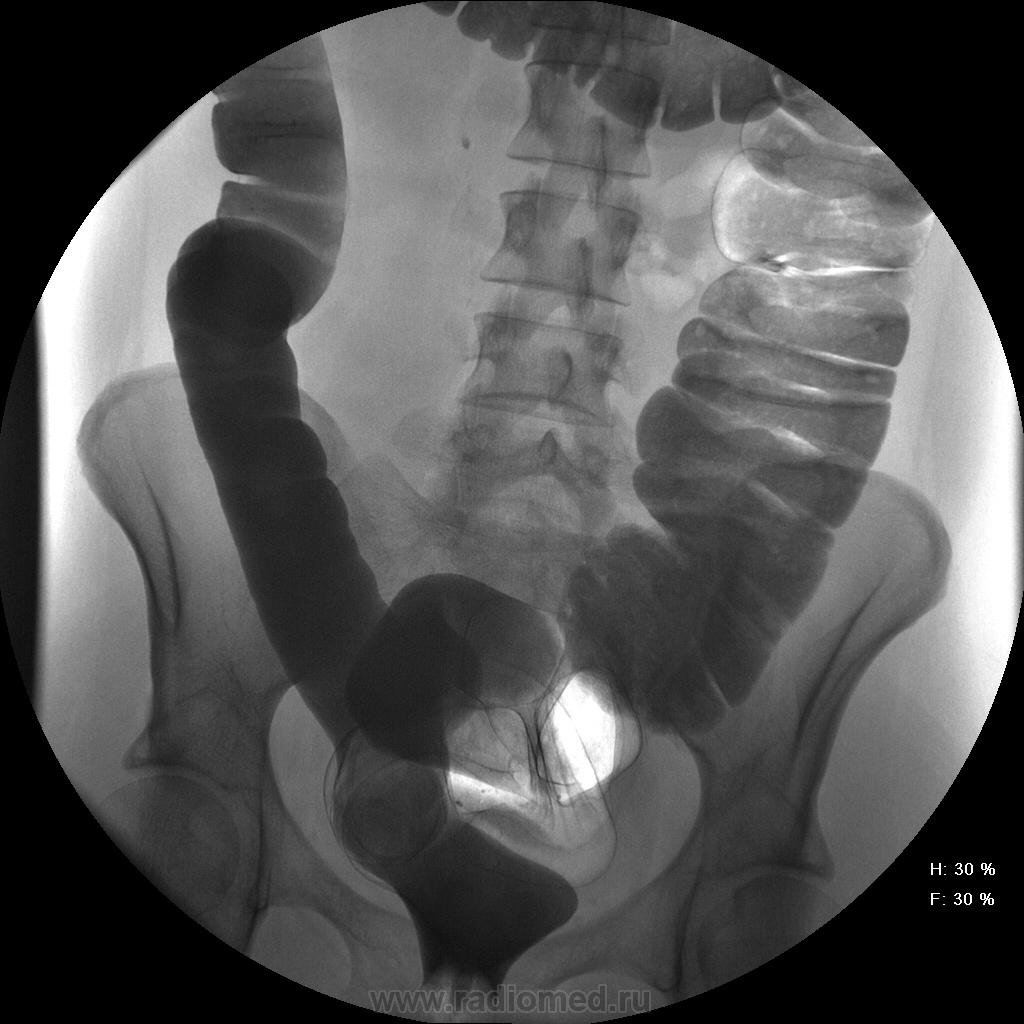

Девушка, 27 лет, жалуется на периодические боли в правой подвздошной области, области паха справа. Во время этого идет нарушение стула - то слабит, то несколько дней не может ходить в туалет, вздутие кишечника. Жалобы несколько лет . Обследованна кем только можно. Хирург посоветовал ирригоскопию. Работа достаточно нервная. До первого случая данных проблем , за неделю, проходила сан лечение в пансионате ( для поднятия общего иммунитета - так говорит), был курс клизм с травами - сама думает, что это не связанно.

Цепочка тенюшек - это наша "гордость)" следы от контраста после гистеросальпингоскопии. чтоб вымыть ,надо разбирать стол , а это только с представителем сименса. вот так.) а правые отделы толстой кишки на расширены? я кроме лополнительной петли сигмы сам ничего не вижу. несколько настораживает некоторое расширение правых отделов кишки- может за счет запоров, которые случаются у девушки? не хочется что то пропустить.

Коллеги, значит пишу долихосигма и все?

Считаю, данных за долихосигму нет.

Слепая кишка в конце исследования, несмотря на её содержимое, заполнилась прилично. А вот гаустрация сигмовидной кишки не сглажена?

Признак долихосигмы - это наличие т.н. симптома "трехстволки", есть это - есть и долихосигма. В данном случае такой вариант имеет место быть.

может и правда гаустрация левых оделов толстой кишки сглажена? интересно, а выраженность гаустрации зависитиот наследственных особенностей - у кого то лучше, у кого то хуже выражена? или все же сглаженность - признак патологии?

Явная сглаженость никак нормой быть не может...в том числе и слева...а уж если мелкая зубчастось, пусть и преходящая...а если и спастические скоращения на большом протящении...а если и неровность и несимметричность гаустр...а если и боль при рентгенопальпации...а если и изменения структуры рельефа...вот тогда и о КОЛИТЕ поговорить можно...